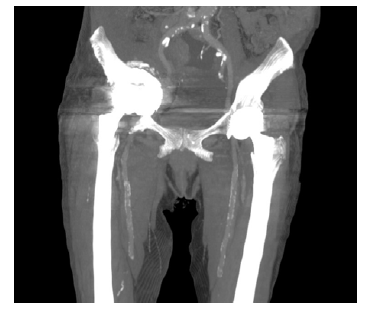

Doente de 80 anos, sexo feminino, com antecedentes pessoais médicos de hipertensão arterial, diabetes mellitus tipo 2, dislipidemia, fibrilhação auricular crónica paroxística, AVC cerebeloso à direita, anemia ferropénica e antecedentes cirúrgicos de laqueação de trompas e cistopexia por laparatomia mediana, prótese de anca bilateral, prótese aorto-aórtica por isquemia crónica dos membros inferiores por doença obstrutiva da aorta abdominal. Por edema assimétrico e impotência funcional do membro inferior direito realizou angio-tomografia computorizada (Angio-TC) pélvica em 11/01 que revelou “extensa trombose da veia ilíaca externa direita, de sugestão aguda (…) migração pélvica do componente acetabular da artroplastia total da coxofemoral direita por loosening com perda parcial da congruência da cabeça femoral”. Coexistem alterações inflamatórias/granulomatosas locais e presença de adenopatias inguinais proeminentes, de provável natureza reativa,” Figura 1 e 2.

Verifica-se protusão do acetábulo à direita, após artoplastia da anca.

Figura 2 Angio-tomografia computorizada em corte coronal, pré-operatória (multiple intensity projection).

Verifica-se intima relação entre os vasos ilíacos e a protusão acetabular